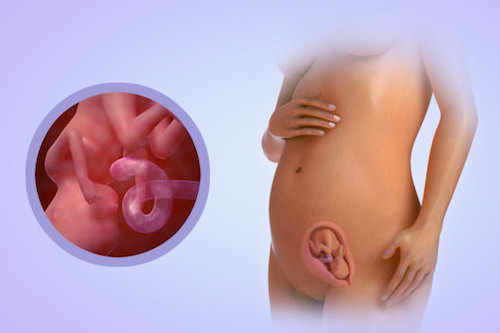

Ви переживаєте вагітність 18 тиждень, половина шляху вже позаду. Ваша дитина росте і міцніє, зміцнюються його кістки, нервова система продовжує розвиватися.

Другий тиждень п'ятого місяця - це і є 18 тиждень вагітності, або другий триместр. Ніяких принципових змін в організмі матері і дитини не відбувається, однак цей період важливий як встановлення невидимого контакту майбутньої мами зі своїм малюком.

Розмір плода до 18 тижня становить в середньому трохи більше 14 см в довжину. Вага малюка - десь близько 200 р Незважаючи на збільшення його росту, він все ще вільно може пересуватися в порожнині матки, перевертатися, ворушити ручками і ніжками. Прийнято вважати, що такі рухи дуже корисні для його розвитку.

У дитинку до 18 тижня повністю сформувалися ручки і ніжки. На пальчиках сформувався унікальний рельєф шкіри, званий відбитком пальців. Активно розвивається головний мозок малюка, а разом з ним і імунна система, яка допомагає плоду потрапляє до нього інфекції.